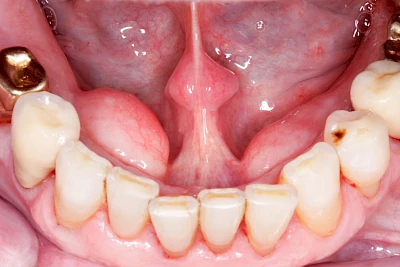

Gehen die Zähne verloren, baut häufig auch der Kieferknochen ab (Knochenschwund). Die Geschwindigkeit und das Ausmaß des Knochenschwundes ist von vielen Faktoren abhängig. Neben der genetischen Veranlagung spielen auch Überbelastungen in Folge, z. B. bei ständigem Knirschen oder Pressen, eine Rolle. Auch wenn Zahnprothesen Tag und Nacht getragen werden, kann die ständige Belastung der Schleimhäute und des Knochens den Knochenschwund beschleunigen.

Aber Achtung: Manche Menschen fühlen sich ohne Zahnprothesen unwohl. Zudem kann es passieren, dass Zahnprothesen (wenn noch eigene Zähne vorhanden sind) nicht mehr passen. Dies gilt vor allem dann, wenn diese Zahnprothesen nicht nur über Nacht, sondern für einen längeren Zeitraum nicht mehr getragen werden.

Auch wenn Zahnprothesen drücken, sollten vor allem Teilprothesen jeden Tag wenigstens für ein paar Minuten getragen werden, damit sich die eigenen Zähne nicht unbeabsichtigt verstellen und die Prothese weiter passt.